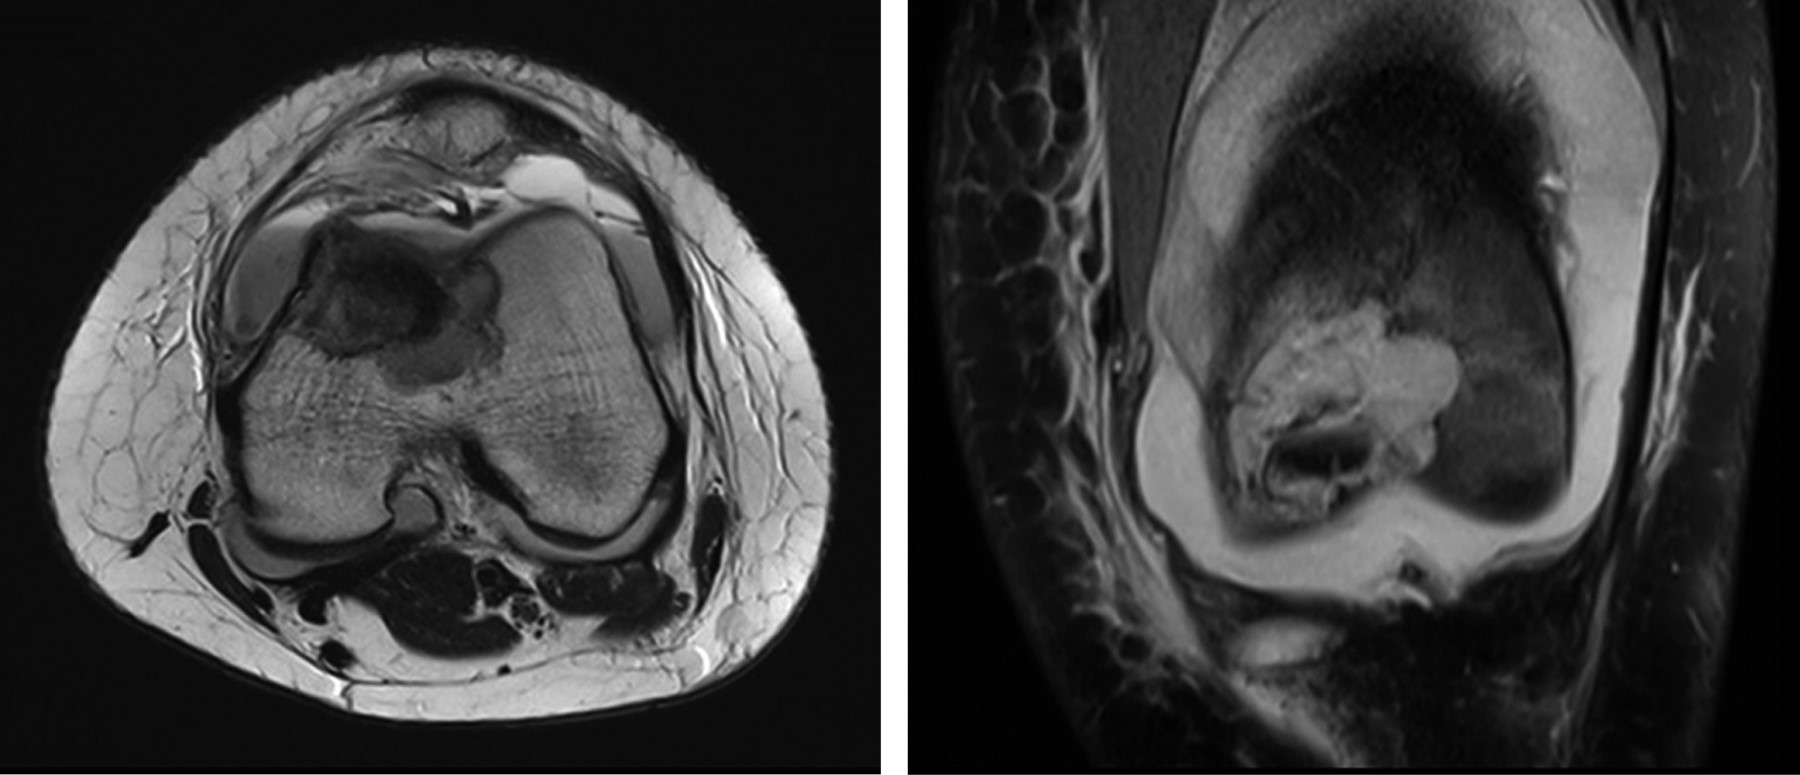

Se realizó el estudio complementario con TAC y RMN; en el cual la TAC de rodilla indicó una imagen lítica metafisaria de fémur distal de bordes circunscritos bien definidos con fractura en hueso patológico, sin colapso de la columna medial (Figura 2) y en la RMN en el corte T2 y supresión grasa, se observó una lesión de márgenes escleróticos sin signos de reacción perióstica, con relleno de aparente densidad líquida levemente heterogéneo, con aparente invasión fisaria, sin compromiso de partes blandas, siendo compatible con neoplasia de origen condral coincidiendo con la sospecha diagnóstica de condroblastoma de fémur distal (Figura 3).

Durante el seguimiento radiológico y clínico estricto, se realizó un control inicial al mes postoperatorio, seguido de controles cada tres meses (Figura 4). Durante el último mes previo al control de los siete meses postoperatorios, la paciente presentó dolor constante afebril y sensación de calor local, sin otros signos de infección. Debido a estos síntomas, se solicitó una RMN de control con contraste, ésta reveló una pequeña lesión endomedular en la metáfisis distal de fémur, sugestiva de un foco de recidiva (Figura 5). Ante este hallazgo, se decidió una nueva intervención en la cual se realizó un segundo curetaje con biopsia, confirmando el diagnóstico de recidiva de condroblastoma. En esta intervención, no se aplicó injerto adicional y se optó por una resección intralesional completa sin adyuvancia.